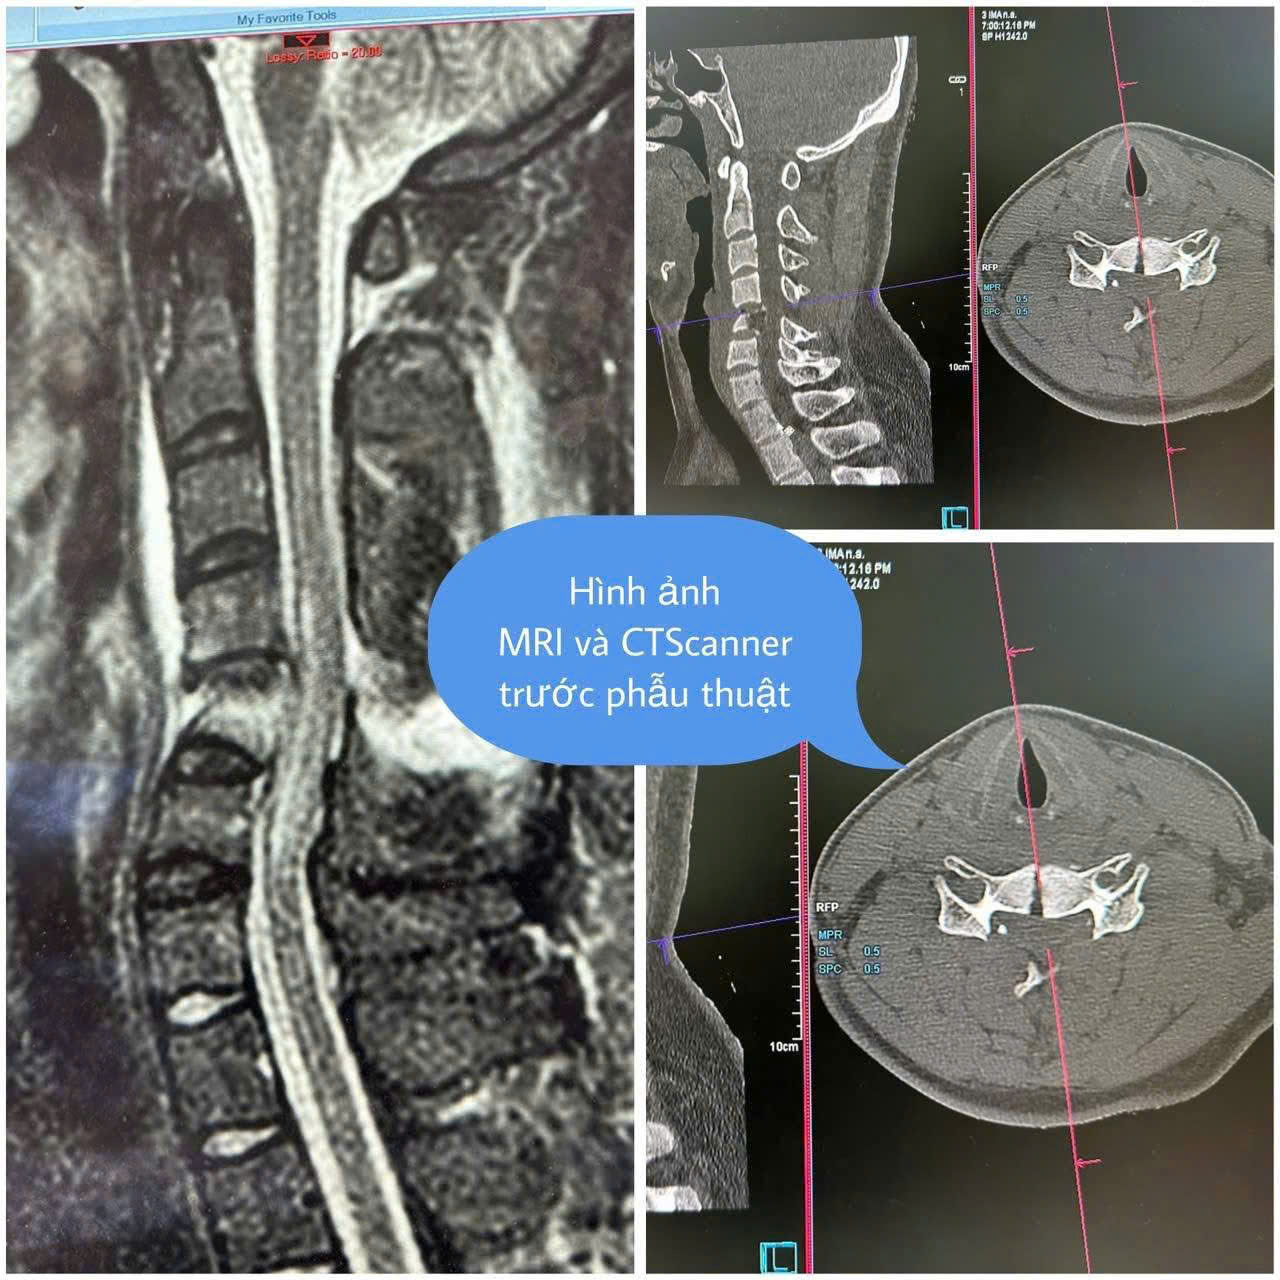

Bệnh nhân nhập viện trong tình trạng liệt tứ chi và bí tiểu cấp tính do bị chèn ép tủy, nguy cơ cao để lại di chứng nếu không điều trị kịp thời. Sau khi thăm khám và thực hiện các cận lâm sàng, bác sĩ xác định bệnh nhân bị gãy nhiều mảnh đốt sống cổ, tổn thương tủy. Với tình trạng nguy kịch của bệnh nhân, ê-kíp bác sĩ Khoa Ngoại cột sống và Khoa Phẫu thuật - Gây mê hồi sức đã tiến hành phẫu thuật cố định bằng vít chân cung cột sống cổ, giải phóng chèn ép tủy cho bệnh nhân. Sau 4 giờ phẫu thuật, ca mổ thành công. Kết quả kiểm tra bằng hình ảnh cho thấy, hệ thống cố định vững chắc, kết hợp xương chính xác từng vị trí. Bệnh nhân sau phẫu thuật hồi phục tốt, có lại cảm giác, đặc biệt người bệnh cử động được tứ chi.